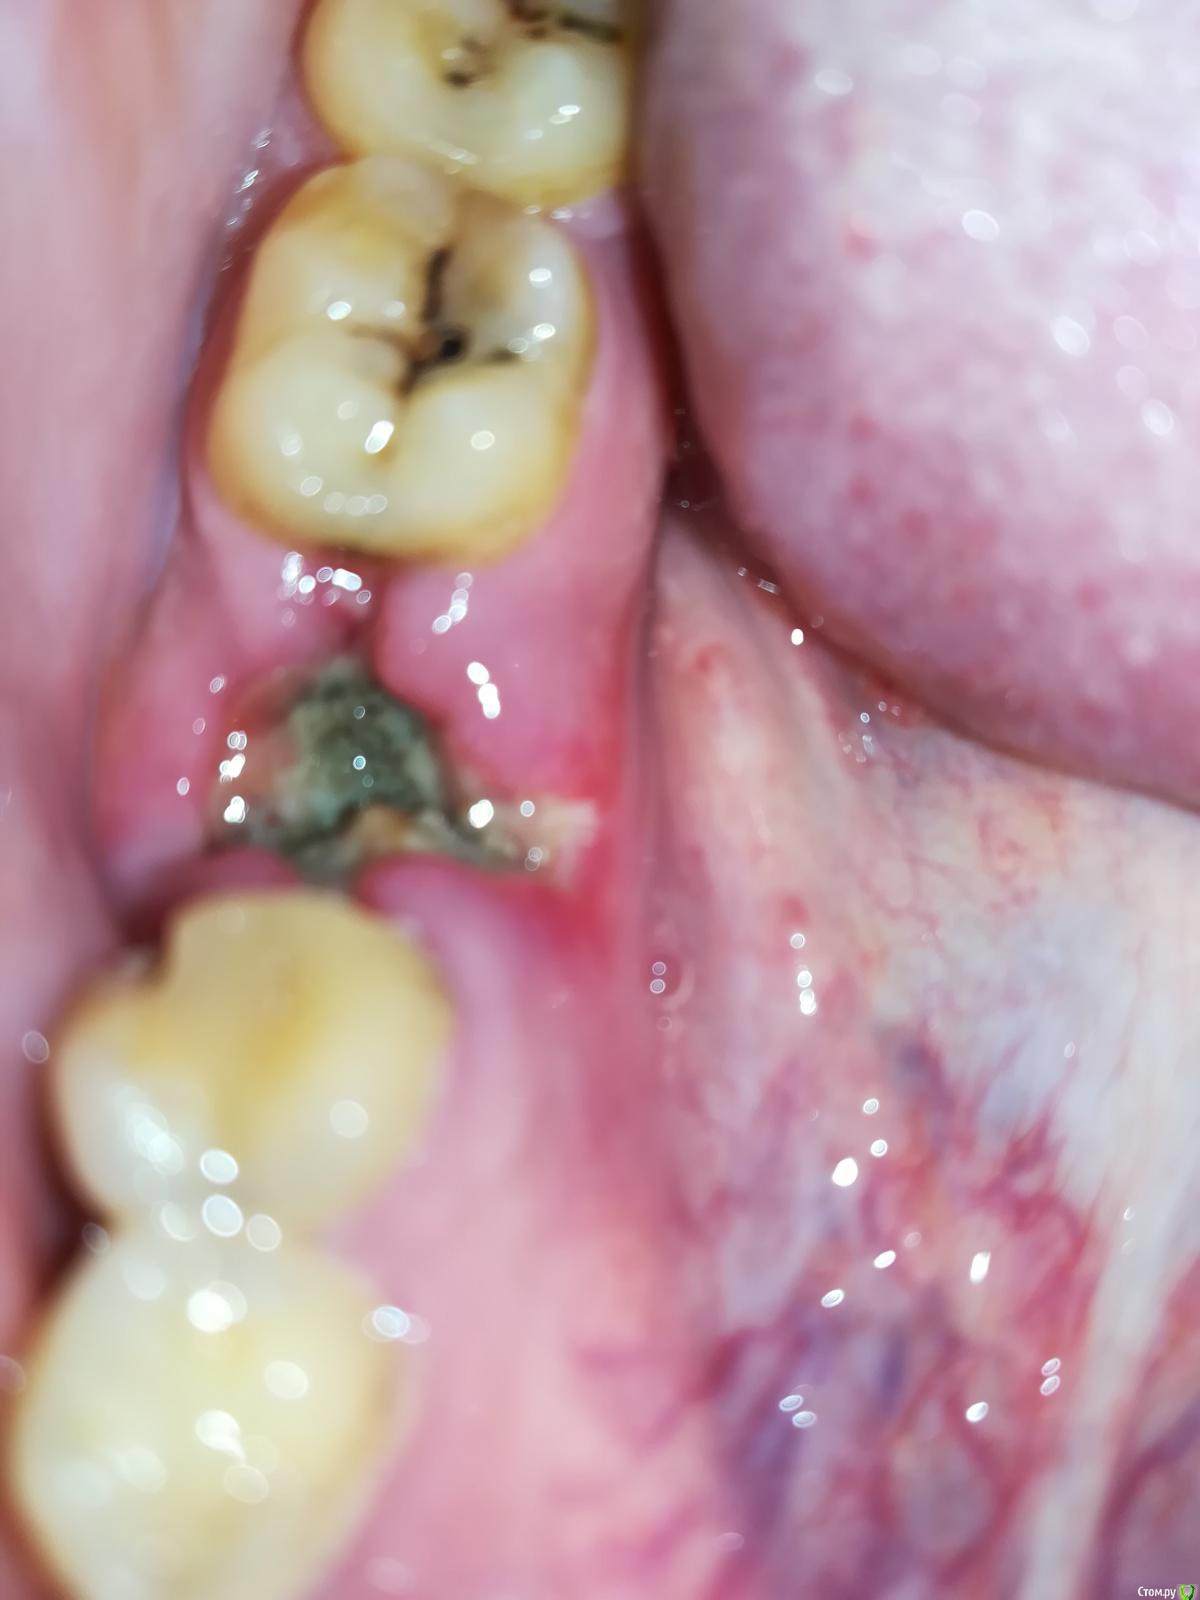

r7zh Опубликовано 1 мая, 2018 Поделиться Опубликовано 1 мая, 2018 (изменено) Здравствуйте! После удаления шестого нижнего зуба прошло 5-6 дней, десна не болят (только первые 2 дня), покраснение тоже отсутствует, температура в норме, по рентген снимку доктор сказал, что удаление прошло хорошо, ничего не осталось. Только беспокоит неприятный запах из лунки.По фото можно определить или нормально проходит заживление? Спасибо, с уважением. Изменено 1 мая, 2018 пользователем r7zh Ссылка на комментарий